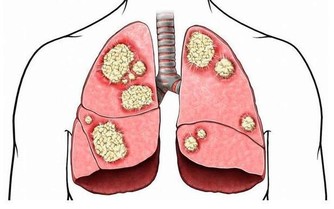

自2010年2月4日,因喉部總有異物感和頸部淋巴結腫痛看病。醫生給我做了淋巴結針吸,及甲功全項檢查。結果為甲狀腺球蛋白為351.正常值應該是0.針吸結果為淋巴有外癌細胞。考慮為轉移癌。2010年2月20日,在北京協和醫院確診為:甲狀腺癌晚期,已經轉移至肺部。CT胸片為有大量結節組織。多為5毫米以下為轉移癌。

2010年3月1日,在醫院住院, 檢查頸部彩超,左側多發結節,大部分鈣化。右側甲狀腺部位有1.6×1.3 cm的腫瘤。2010年3月8日,在醫院行甲狀腺右側全切及左側淋巴清掃術。手術過程中斷紮帶狀肌,斷扎甲狀腺動靜脈,斷扎甲狀腺側韌帶,斷開左側胸鎖乳突肌,斜方肌,斷扎頸外靜脈及頸深筋膜。斷扎頸叢神經根行淋巴清掃術。術後病理結果為甲狀腺高分化乳頭狀癌,淋巴2/5轉移。術後15天進行了碘131治療,現在正在進行第四次碘131隔離治療。

等到我發現,我的病已經到了晚期了。一家著名中醫館的膏穴療法專家告訴我,甲狀腺癌細胞,從微粒長到米粒大小需要十年,而從米粒大小長到花生米大小只需幾個月。我不知道我的甲狀腺癌細胞是從什麼時候開始復發轉移的,總之是晚期的晚期了。